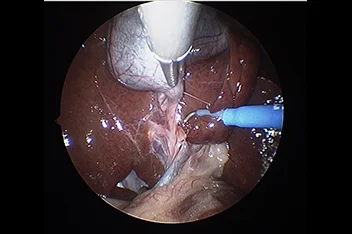

부울경 최초 ‘양방향 척추내시경’ 도입

정밀하고 덜 아픈 척추 수술의 새로운 패러다임

양방향 척추 내시경 BESS, Biportal Endoscopic Spine Surgery

기존의 단일 포털 내시경(uniportal endoscopy)의 한계를 극복한

정밀한 양손 작업이 가능한 최소침습 기술입니다.

리본동물의료센터 2025년 1월부터 부울경 최초로 양방향 척추 내시경을 도입해왔으며, 영남권 최다 임상 CASE를 축적하고 있습니다.

양방형 척추 내시경 수술의 핵심 장점

• 정밀한 수술 조작

• 근육 인대 손상 최소화

• 절개 최소화

• 빠른 회복과 낮은 통증

• 고배율 직시 시야 확보